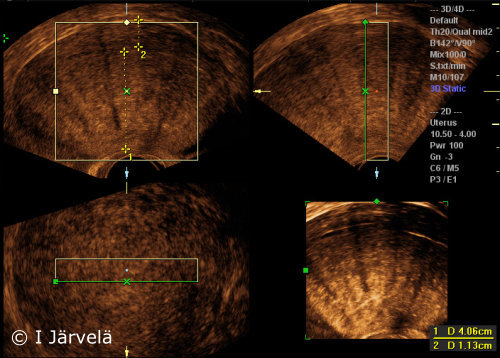

Adenomyosis (Ultrasound Scan)

Adenomyosis (ultrasound scan). Note the disparity of uterine wall thicknesses and theinhomogeneity of myometrial echo.

Picture: Ilkka Järvelä; text: Dimitrios Scordas